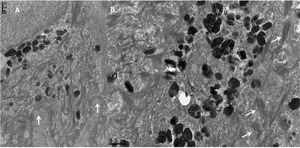

A MET demonstrou estruturas epidérmicas normais, como desmossomos, filamentos de citoqueratina, membrana basal e hemidesmossomos (fig. 3). Observou‐se elevada quantidade de melanossomas nos queratinócitos (fig. 3B), que mediam 0,38 a 0,67nm, além de variação na sua forma e no tamanho (figs. 3B, 4A e 5).

Com grandes ampliações, puderam ser observados recortes no contorno dos melanossomas (fig. 4), bem como um contorno melanossomal irregular (fig. 5), em contraste com os melanossomas normais, que apresentam contorno regular e formato oval (fig. 5, detalhe).